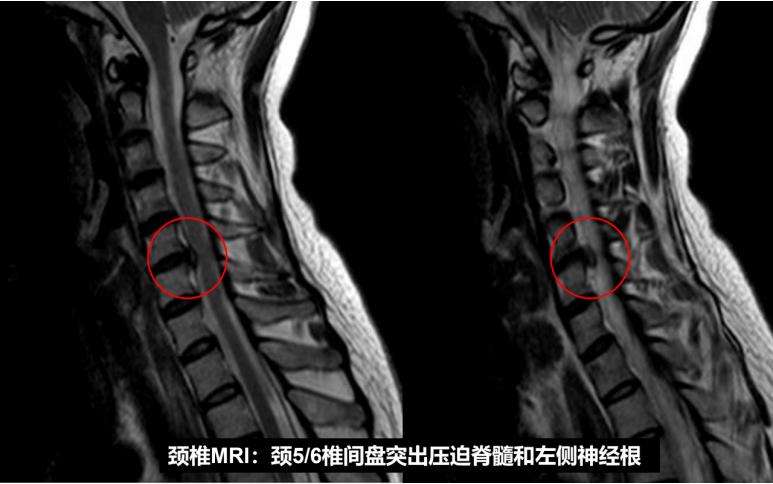

为明确诊断,卢祺主治医师为患者安排了颈椎CT和MRI检查。影像结果提示患者颈5/6节段存在椎间盘突出,压迫左边的神经根,导致患者颈肩痛、手麻。患者的症状、体征和影像学检查都很典型,符合神经根型颈椎病的诊断。